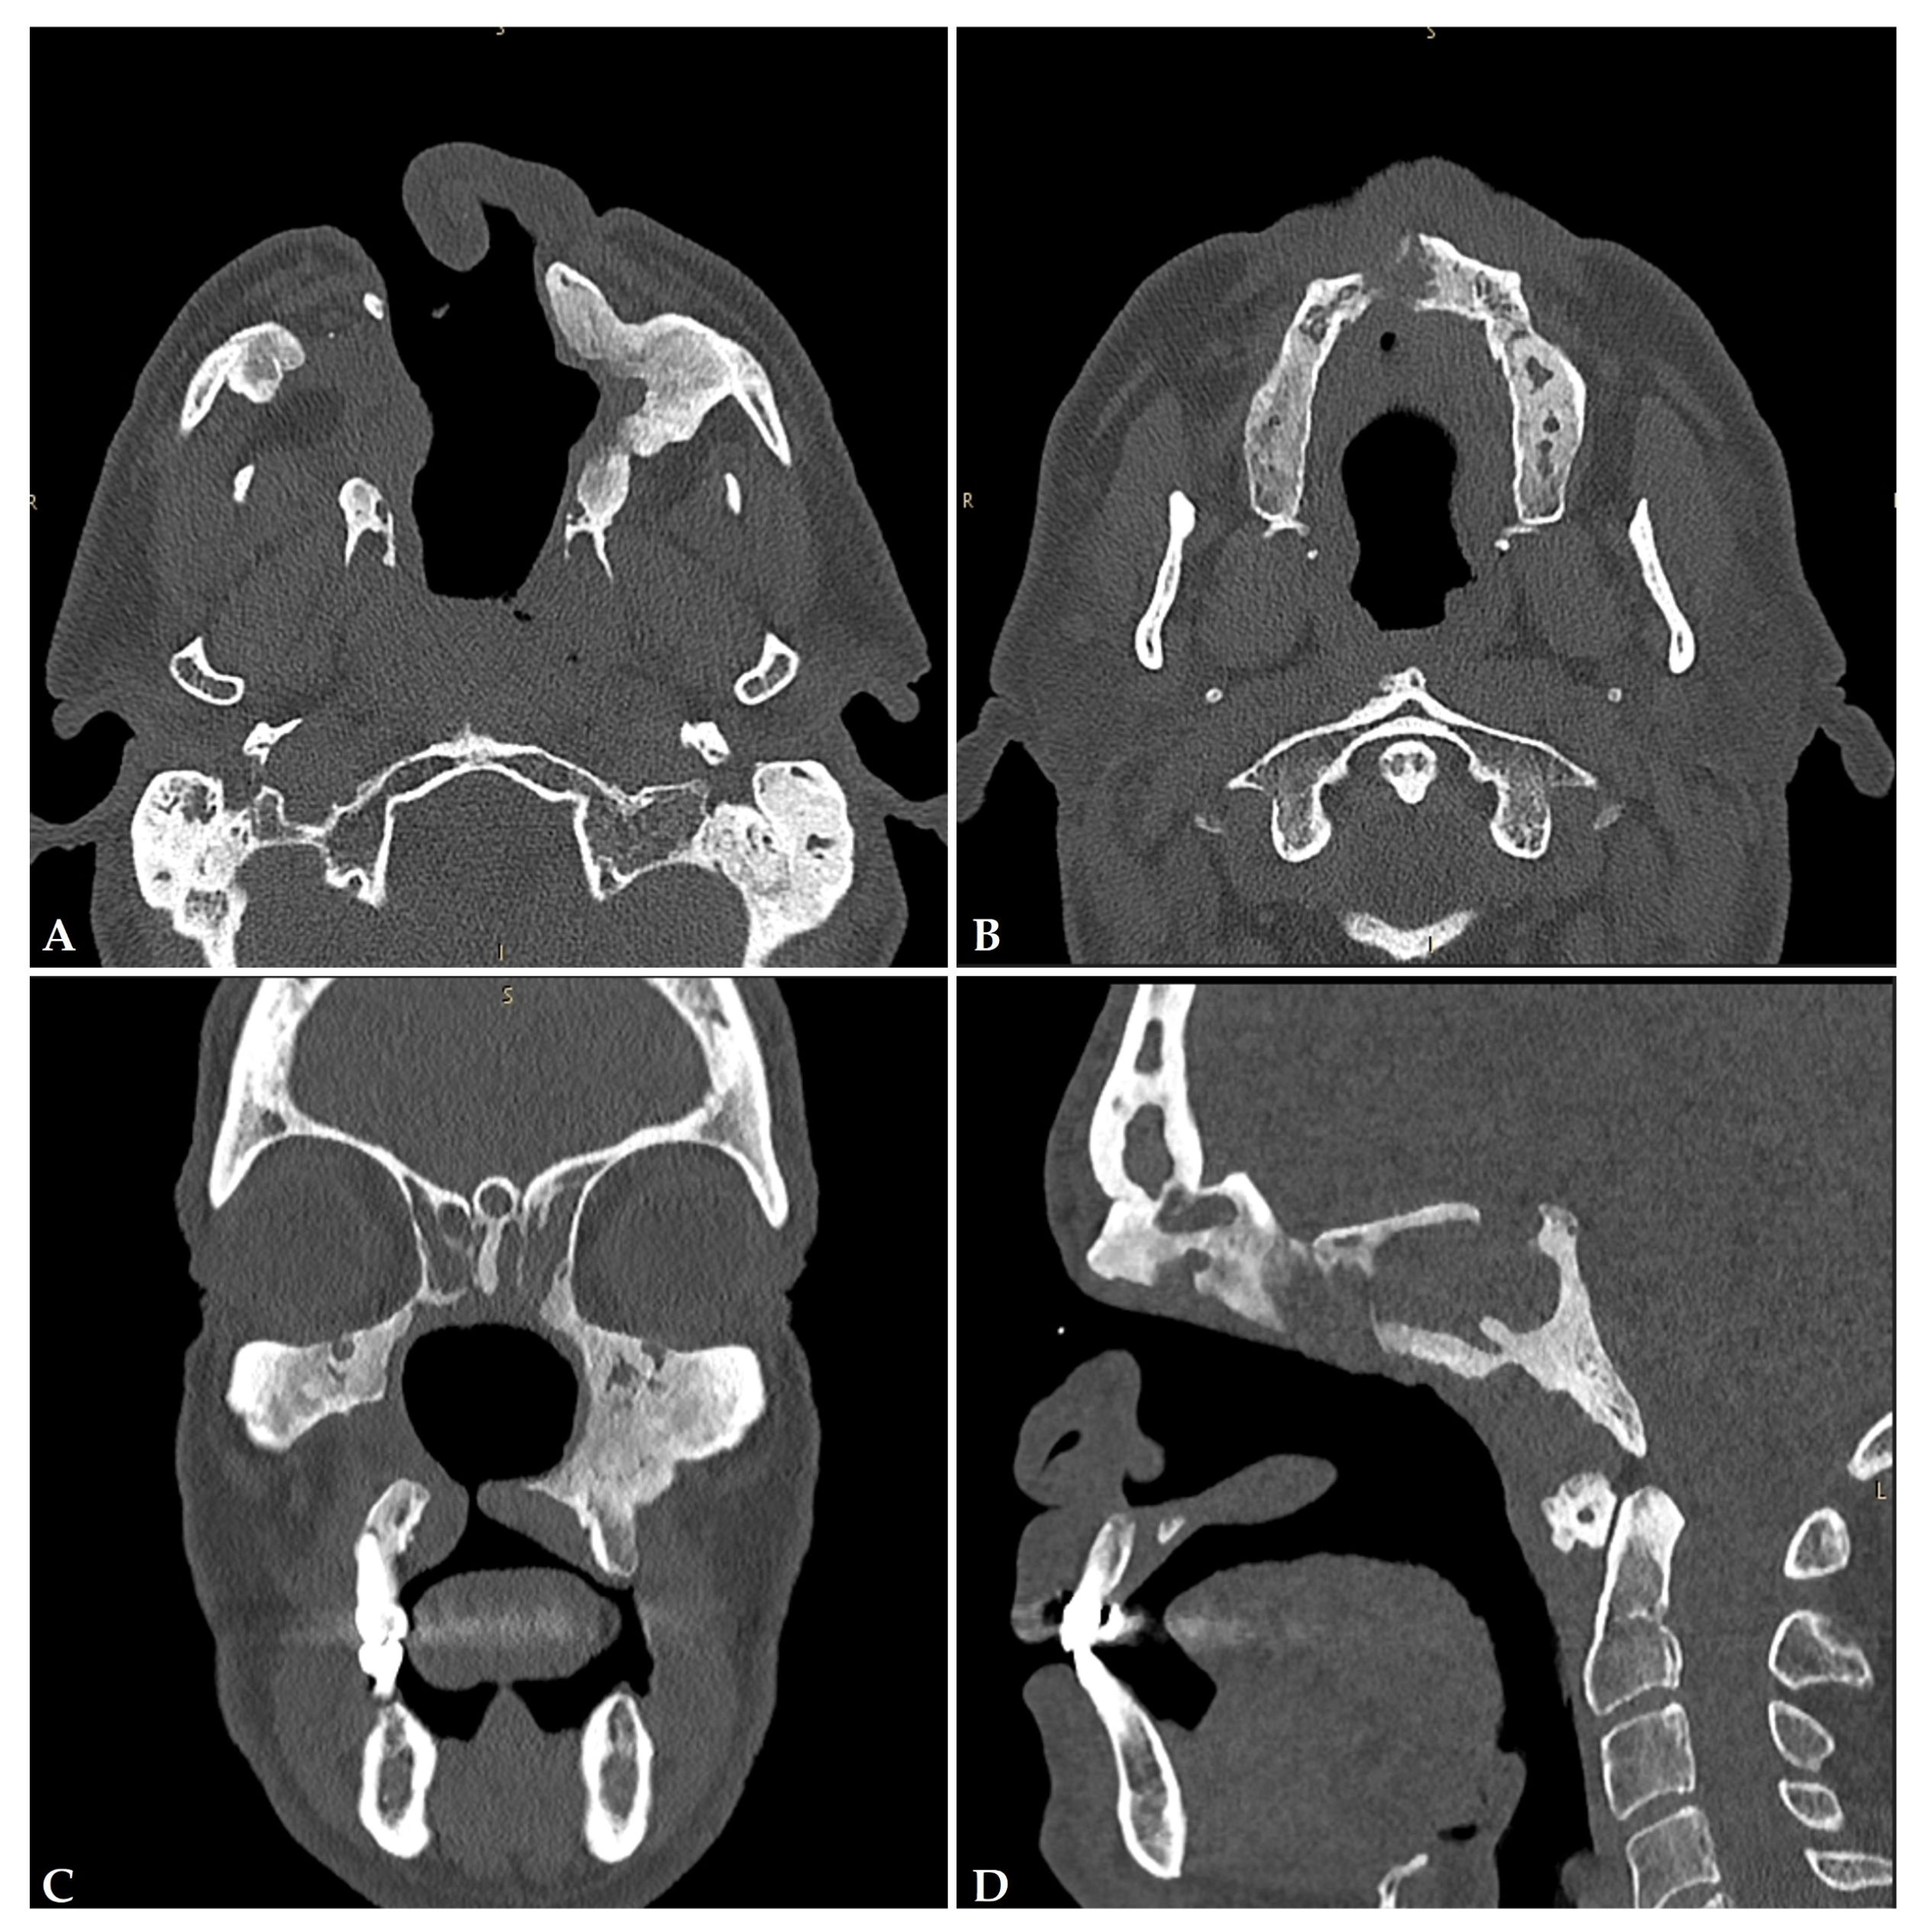

3.1.4. Imaging

- Nitro, L.; Pipolo, C.; Fadda, G.L.; Allevi, F.; Borgione, M.; Cavallo, G.; Felisati, G.; Saibene, A.M. Distribution of cocaine-induced midline destructive lesions: Systematic review and classification. Eur. Arch. Otorhinolaryngol. 2022, 279, 3257–3267. [Google Scholar] [CrossRef] [PubMed]

| Classification Grade | Localization | Patients in the Nitro et al. [24] Systematic Review |

|---|---|---|

| 1 (middle) | Nasal septum | 126 (99.2%) |

| 2 A (inferior third of the sinonasal complex) | Grade 1 + inferolateral district (inferior turbinate and Maxillary-sinus medial wall, nasolacrimal duct) | 75 (59%) |

| 2 B (inferior third of the sinonasal complex) | Grade 1 + palate (nasal floor) | 38 (29.9%) |

| 3 (middle third of the sinonasal complex) | Grade 2 + ethmoid bone, middle turbinate and superior turbinate | 29 (22.8%) |

| 4 (neurocranial structures) | Grade 3 + neurocranium (lamina papyracea, orbit base or skull base) | 10 (7.9%) |